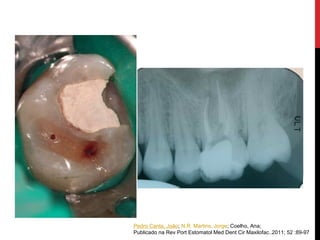

Pedro Canta, João; N.R. Martins, Jorge; Coelho, Ana;

Publicado na Rev Port Estomatol Med Dent Cir Maxilofac..2011; 52 :89-97